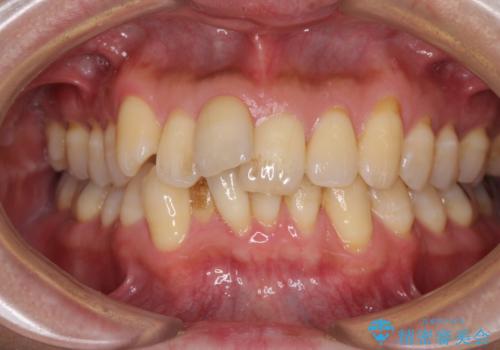

前歯のデコボコ ワイヤー装置での短期間治療

- 前歯のデコボコを気にして来院された患者様です。

インビザラインまたはワイヤー装置、どちらでも対応可能でしたが、自己管理の少なさ、期間の短さから、ワイヤー装置による矯正治療を行うこととしました。